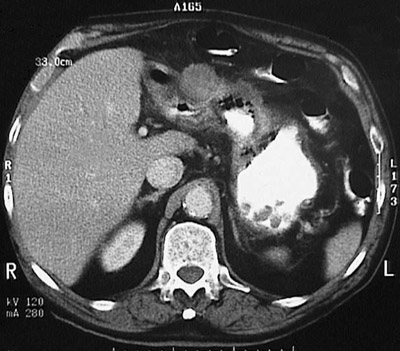

This abdominal CT scan with contrast reveals a mass lesion distorting the gastric antrum. This is an adenocarcinoma. This patient had H. pylori infection for many years.